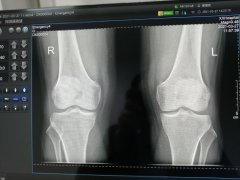

DR平板暗校正和亮校正的区别

在 DR(数字 X 射线摄影)系统中,平板探测器是关键部件。暗校正和亮校正都是为了优化探测器的性能,以获得高质量、准确的图像。 暗校正(Dark Calibration) 也称为暗场校正。它主要...更多 -